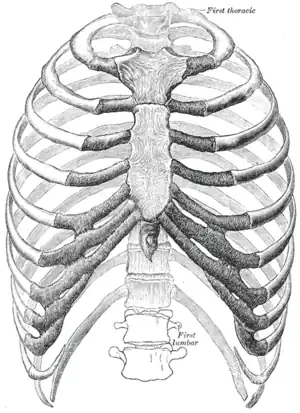

The human rib cage (Source: Gray's Anatomy of the Human Body, 20th ed. 1918) | |

Human ribs are flat bones that form part of the rib cage to help protect internal organs. Humans usually have 24 ribs, in 12 pairs.[2] 1 in 500 people have an extra rib known as a cervical rib. People may have a cervical rib on the right, left or both sides.[3] All are attached at the back to the thoracic vertebrae and are numbered from 1 to 12 according to the vertebrae to which they attach. The first rib is attached to thoracic vertebra 1 (T1). At the front of the body, most of the ribs are joined by costal cartilage to the sternum. Ribs connect to vertebrae at the costovertebral joints.[4]

Rib cage

The first seven sets of ribs, known as "true ribs", are attached to the sternum by the costal cartilages. The first rib is unique and easier to distinguish than other ribs. It is a short, flat, C-shaped bone, and attaches to the manubrium.[6] The vertebral attachment can be found just below the neck at the first thoracic vertebra, and the majority of this bone can be found above the level of the clavicle. Ribs 2 through 7 then become longer and less curved as they progress downwards.[7] The following five sets are known as "false ribs", three of these sharing a common cartilaginous connection to the sternum, while the last two (eleventh and twelfth ribs) are termed floating ribs.[2] They are attached to the vertebrae only, and not to the sternum or cartilage coming off of the sternum.

In general, human ribs increase in length from ribs 1 through 7 and decrease in length again through rib 12. Along with this change in size, the ribs become progressively oblique (slanted) from ribs 1 through 9, then less slanted through rib 12.[7]